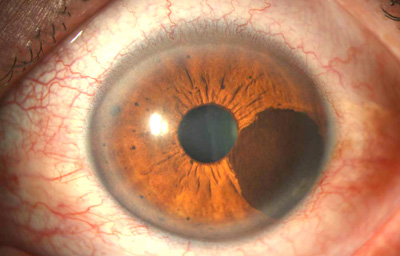

Melanocitomas

Melanocitoma es una lesión benigna, profundamente pigmentada, variante del, nevus uveal que fue originalmente descrito por Zimmerman y Garron en 1962 en el nervio óptico; ahora se sabe que puede aparecer en cualquier lugar del tracto uveal.

Son masas con algo de elevación, con pigmento marrón oscuro casi negro, frecuentemente con apariencia de “ montículo de arena negra”. Sus células son ovoides con núcleos uniformes, pequeños y muy pigmentados. pueden generar satélites en el estroma o en el ángulo de la cámara anterior. Pueden evolucionar a Melanoma (30)

Archivo Fotográfico Dr. Francisco Barraquer. 2012

Archivo Fotográfico Dr. Francisco Barraquer. 2017

Estudio comparativo